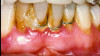

Bleeding: not a good predictor of disease activity. Bleeding on probing (BOP) represents an inflammatory infiltrate in the connective tissue, a reduction of collagen, and ulceration of the pocket's epithelial lining (Figure 2 and Figure 3).18 However, bleeding does not indicate the severity of periodontal lesions, and BOP is not a good predictor of disease activity.19 The term "disease activity" denotes there is ongoing clinical attachment and/or bone loss. Conversely, the absence of BOP is a good forecaster of clinical health and long-term tooth retention.19 Thus, BOP is an excellent indicator of the need for therapy, and its elimination is an important clinical endpoint.

Fig 2. Gingival biopsy from a site that bled upon probing. Note an inflammatory infiltrate (dark area) and reduction of collagen (whitish area).

Figure 2